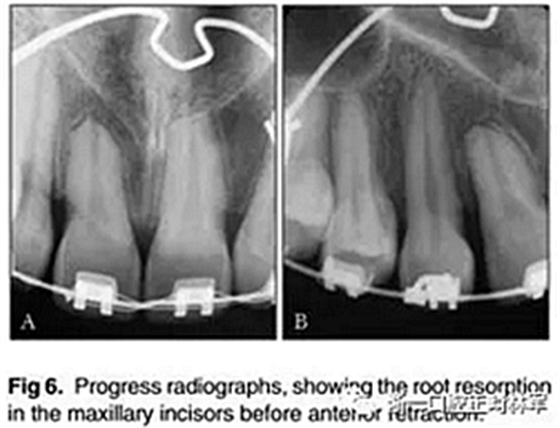

此時,拍攝隨訪的根尖片(圖6)。這些圖像表現(xiàn)出根吸收增加的證據(jù),特別是在先前已經(jīng)診斷出根部縮短的上頜中切牙中。因此,牙齒移動被暫停了90天,然后逐漸恢復(fù),每隔2個月進(jìn)行一次正畸復(fù)診。